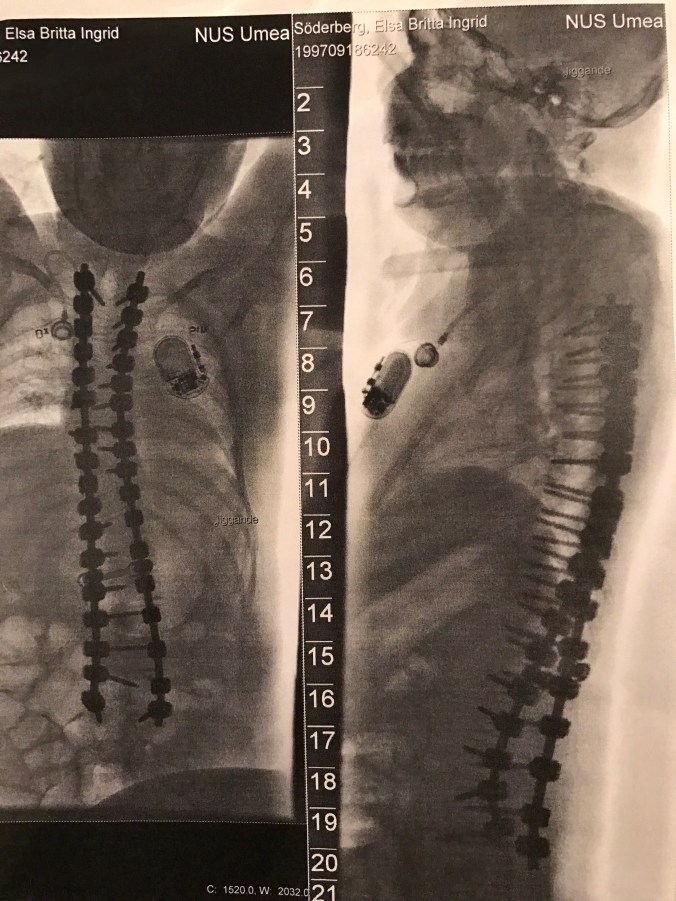

För att lungorna skulle få plats att växa så kunde ingen steloperation göras på en gång utan en typ av stag skulle skruvas fast på några ställen av ryggraden,stagen skulle sedan förlängas genom en operation varje halvår tills ryggen blivit tillräckligt lång.

Vi måste vänta,men det görs ytterligare tre förlängningar med komplikationer ,fast inte så kraftiga som den första .

Nu har Elsas rygg stelopererats,så inga fler ryggoperationer behövs.